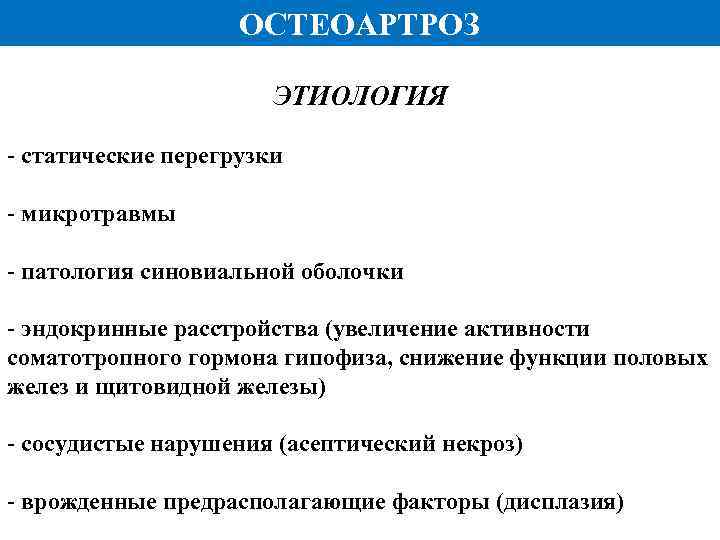

ОСТЕОАРТРОЗ ЭТИОЛОГИЯ - статические перегрузки - микротравмы - патология синовиальной оболочки - эндокринные расстройства (увеличение активности соматотропного гормона гипофиза, снижение функции половых желез и щитовидной железы) - сосудистые нарушения (асептический некроз) - врожденные предрасполагающие факторы (дисплазия)

ОСТЕОАРТРОЗ ЭТИОЛОГИЯ - статические перегрузки - микротравмы - патология синовиальной оболочки - эндокринные расстройства (увеличение активности соматотропного гормона гипофиза, снижение функции половых желез и щитовидной железы) - сосудистые нарушения (асептический некроз) - врожденные предрасполагающие факторы (дисплазия)